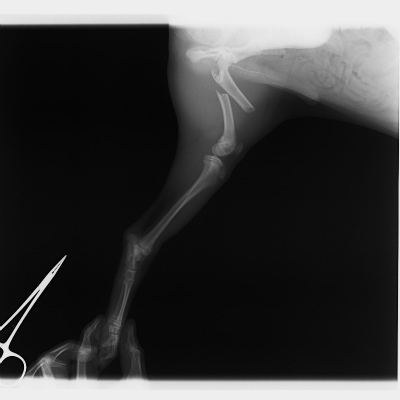

最初に紹介する写真は室内で転んで起きてしまった小型犬の橈尺骨(前足の骨)の骨折です。

骨折用の金属プレートを用いた手術によって、整復しました。